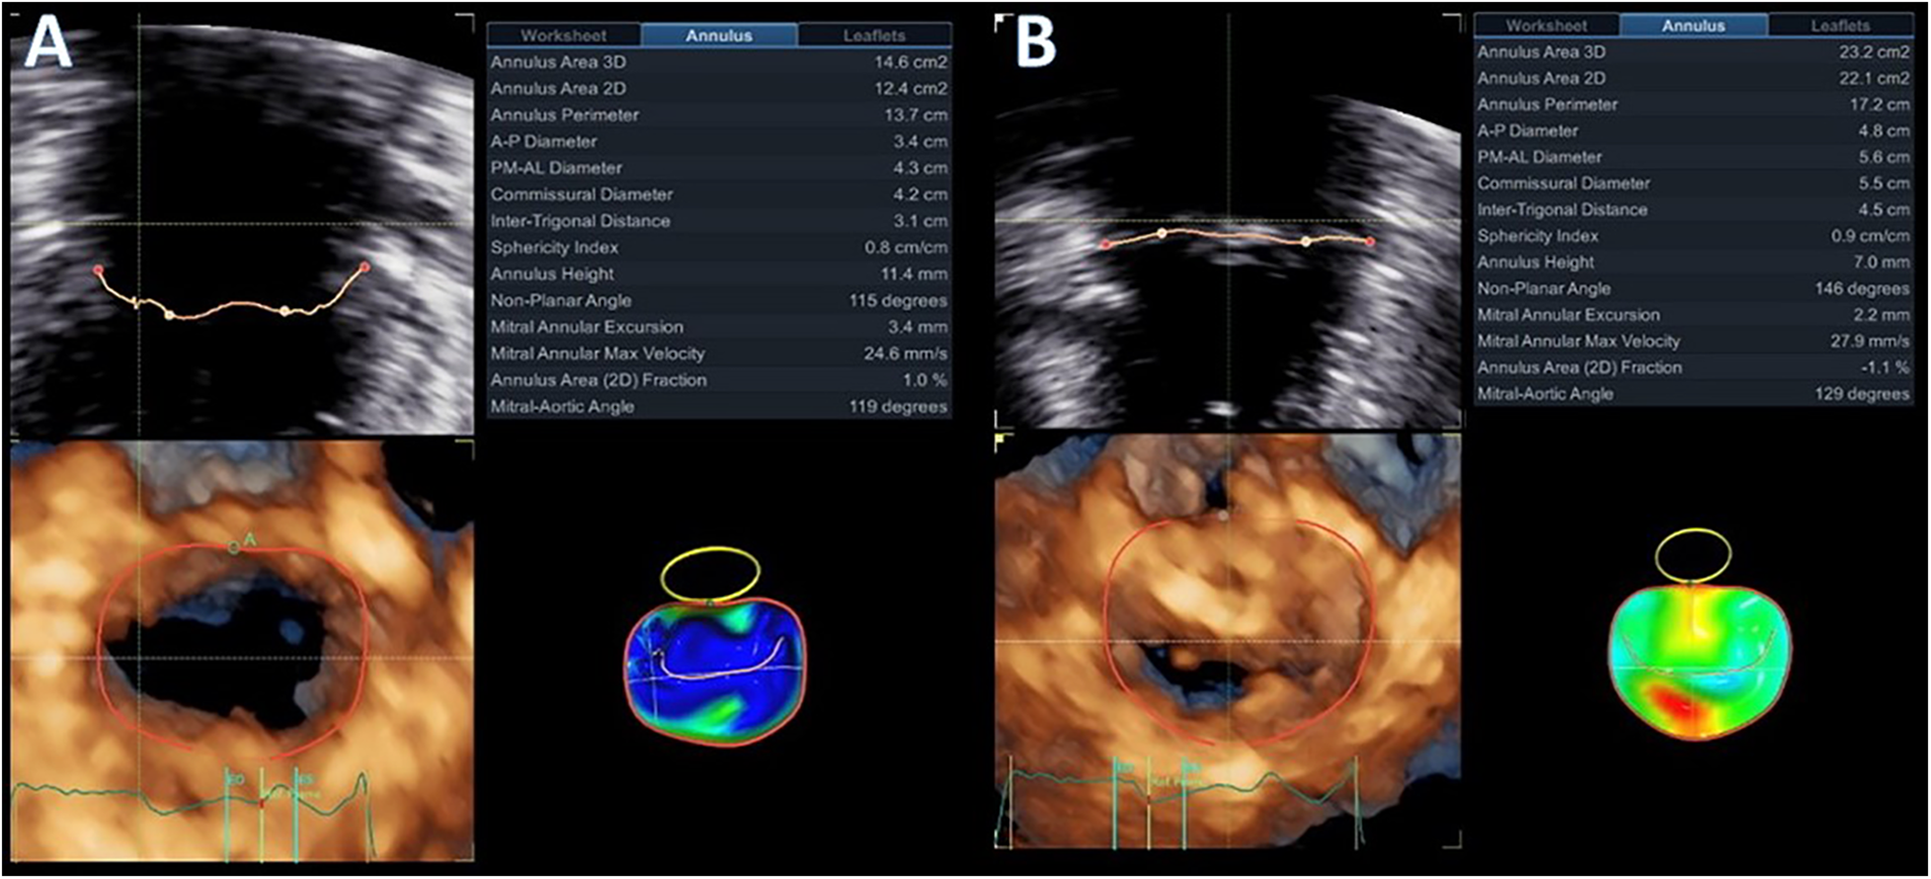

Advanced mitral valve assessment was performed with the AutoMVQ method that provided the measurements of the leaflets and the annulus, using an apical four-chamber view, focused on the mitral valve with 4D zoom and a frame rate of >12 vps. By default, AutoMVQ creates the mitral valve model using a middle reference frame between end-diastole and end-systole. Since the requested information for MAD syndrome is the dimension changes between diastole and systole, we had to manually adjust the systolic and diastolic frames twice and provide two different mitral valve quantification (MVQ) models. A direct comparison of the systolic and diastolic models allows us to understand the dynamic annulus changes in MAD syndrome. In our patient, this method confirmed (1) the flattening of the saddle-shaped annulus during the systole and (2) the systolic expansion. In particular, the annulus area increased from 14.6 cm2 to 23.2 cm2, the perimeter from 13.7 cm to 17.2 cm, the anteroposterior diameter from 3.4 cm to 4.8 cm, and the commissural diameter from 4.2 cm to 5.5 cm. Meanwhile, the annulus height decreased from 11.4 cm to 7.0 cm (Figure 4). The disjunction arc of the valve was easily demonstrated by an “en face” 3D ventricular view of the mitral valve where the extent of the arc was assessed by measuring the circumference of the posterior annulus involved within the disjunction. Volume rendering views can reveal the actual part of the free posterior wall of the left ventricle that is separated from the annulus and the atrium (Figures 1C,D).

Figure 4

Diastolic (A) and systolic (B) mitral valve quantification (MVQ) models showing the dynamic changes and the systolic expansion and flattening of the mitral annulus.

A standard 2D parasternal long-axis view was the first image that was used to confirm the presence of MAD syndrome by the “uncoupling” of the posterior ventricular wall from the hinge point of the posterior mitral annulus. A distance of more than 5 mm is usually considered to be diagnostic for the presence of MAD (14). 3D-TTE was able to provide detailed information about the presence and extent of the disjunction arc, the systolic expansion, and the flattening of the saddle-shaped annulus. The extent of the disjunction arc correlates with the severity of MR and the abnormal dynamics of the valve (6). It is well established from previous publications (6, 13, 24) that at the end-diastole, the annulus dimensions are at their maximum, with the anteroposterior diameter and annulus area presenting the greater change. Physiologically, the annulus contracts rapidly at the early systole and then starts to expand. In normal subjects, the end-systolic annulus area is smaller than the end-diastolic one (6). Patients with myxomatous valve disease have larger annulus dimensions, the valve expands even more at the late-systolic period, but the overall annulus area does not reach the end-diastolic measurements (6, 25). In MAD syndrome, on the other hand, the baseline dimensions of the annulus are increased. There is still early systolic contraction of the valve, but, afterward, there is overexpansion of the annulus, with dimensions that exceed the diastolic ones (25). Manual adjustments of the standard MVQ methodology were able to appreciate the systolic expansion and flattening of the annulus by measuring all annulus dimensions and height changes throughout the cardiac cycle. The two frames that we used were the end-diastolic and end-systolic ones to be in agreement with previous publications that analyzed the annulus dynamics.